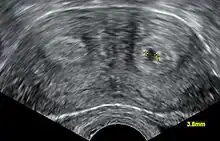

Diagnosis of bicornuate uterus typically involves imaging of the uterus with 2D or 3D ultrasound, hysterosalpingography, or magnetic resonance imaging (MRI). On imaging, a bicornuate uterus can be distinguished from a septate uterus by the angle between the cornua (intercornual angle): less than 75 degrees in a septate uterus, and greater than 105 degrees in a bicornuate uterus. Measuring the depth of the cleft between the cornua (fundal cleft) may also assist in diagnosis; a cleft of over 1 centimetre (0.39 in) is indicative of bicornuate uterus.[2]